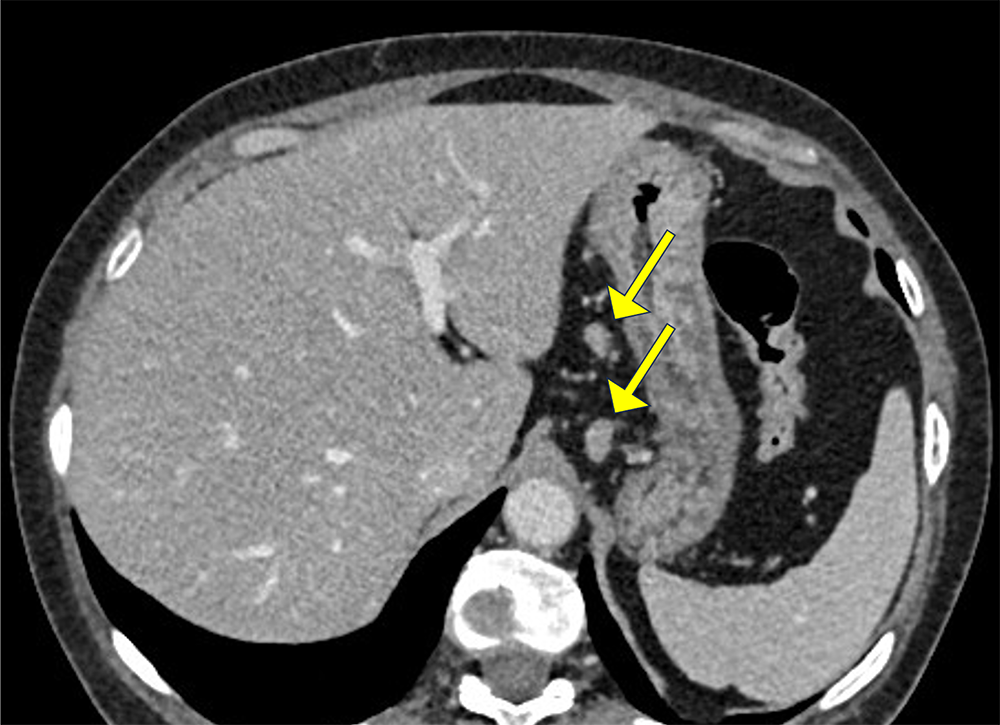

胃体下部小弯側に早期動脈相で他の粘膜面と比較して造影効果の強い領域が認められる。指摘されている胃癌病変を見ているものと考えられる。

胃周囲にはリンパ節と考えられる13mm程度の結節病変を複数個認め、リンパ節転移が疑われる。腹部傍大動脈域に病的有意なリンパ節腫大は認められない。本症例は、腹腔鏡下幽門側胃切除術が施行され、進行胃癌および領域リンパ節転移と診断された。

早期動脈相では、血管走行(動脈)の把握のため、高い造影効果を期待し低管電圧(70kV)を用いている。また低管電圧によるノイズの増加に対しては、2管球(Dualpower)を使用し高出力で撮影し、更に画像再構成はMBIRを用いている。

胃癌に対する根治切除のアプローチ法はこの数年で大きく変わり、早期胃癌を中心に内視鏡治療や腹腔鏡下胃切除、ロボット支援手術が普及しつつある。これらの手術は拡大された術野での出血の少ない精緻なリンパ節廓清が特徴であるが、俯瞰した術野での病変進展範囲の把握が困難になるという課題もある。そのため、術前に十分なシミュレーションを行うために造影CTによる3D画像は有用である。正確な3D画像を作成することで外科医は血管走行を事前に把握でき、出血の回避や多臓器損傷のリスクを減少させることが可能になる。

3D画像は、息止めによる早期動脈相と門脈相の位置ずれがあった場合は、非剛体補正による位置合わせを行う。動脈は腹腔動脈からの左胃動脈、右胃動脈の起始部や大網動脈の走行、門脈では左胃静脈の流入位置を描出することが求められる。また、膵臓や脾臓の実質臓器も3D画像に含めることで、手術時の視野をイメージできるよう配慮している。